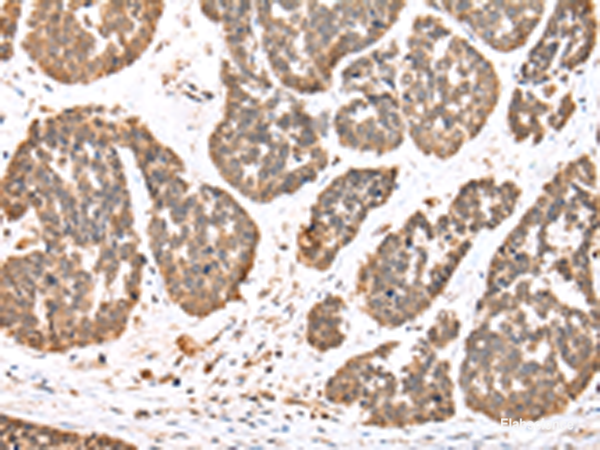

Product information "Anti-DDX58"

DEAD box proteins, characterized by the conserved motif Asp-Glu-Ala-Asp (DEAD), are putative RNA helicases which are implicated in a number of cellular processes involving RNA binding and alteration of RNA secondary structure. This gene encodes a protein containing RNA helicase-DEAD box protein motifs and a caspase recruitment domain (CARD). It is involved in viral double-stranded (ds) RNA recognition and the regulation of immune response. Protein function: Innate immune receptor that senses cytoplasmic viral nucleic acids and activates a downstream signaling cascade leading to the production of type I interferons and proinflammatory cytokines. Forms a ribonucleoprotein complex with viral RNAs on which it homooligomerizes to form filaments. The homooligomerization allows the recruitment of RNF135 an E3 ubiquitin-protein ligase that activates and amplifies the RIG-I-mediated antiviral signaling in an RNA length-dependent manner through ubiquitination-dependent and -independent mechanisms (PubMed:28469175, PubMed:31006531). Upon activation, associates with mitochondria antiviral signaling protein (MAVS/IPS1) that activates the IKK-related kinases TBK1 and IKBKE which in turn phosphorylate the interferon regulatory factors IRF3 and IRF7, activating transcription of antiviral immunological genes including the IFN-alpha and IFN-beta interferons (PubMed:28469175, PubMed:31006531). Ligands include 5'- triphosphorylated ssRNAs and dsRNAs but also short dsRNAs (<1 kb in length). In addition to the 5'-triphosphate moiety, blunt-end base pairing at the 5'-end of the RNA is very essential. Overhangs at the non-triphosphorylated end of the dsRNA RNA have no major impact on its activity. A 3'overhang at the 5'triphosphate end decreases and any 5'overhang at the 5' triphosphate end abolishes its activity. Detects both positive and negative strand RNA viruses including members of the families Paramyxoviridae: Human respiratory syncytial virus and measles virus (MeV), Rhabdoviridae: vesicular stomatitis virus (VSV), Orthomyxoviridae: influenza A and B virus, Flaviviridae: Japanese encephalitis virus (JEV), hepatitis C virus (HCV), dengue virus (DENV) and west Nile virus (WNV). It also detects rotaviruses and reoviruses. Also involved in antiviral signaling in response to viruses containing a dsDNA genome such as Epstein-Barr virus (EBV). Detects dsRNA produced from non-self dsDNA by RNA polymerase III, such as Epstein-Barr virus- encoded RNAs (EBERs). May play important roles in granulocyte production and differentiation, bacterial phagocytosis and in the regulation of cell migration. [The UniProt Consortium]

| Application: | IHC, ELISA |